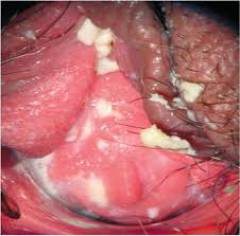

- Выполняет пальцевое влагалищное исследование.

- Вводит гинекологическое зеркало во влагалище для осмотра. Эта процедура может быть неприятной, а при наличии заболеваний — болезненной. Гинеколог оценивает характер выделений и состояние слизистой оболочки (покраснение, отек, утолщение) влагалища, вульвы и шейки матки.

- Берет необходимые анализы.